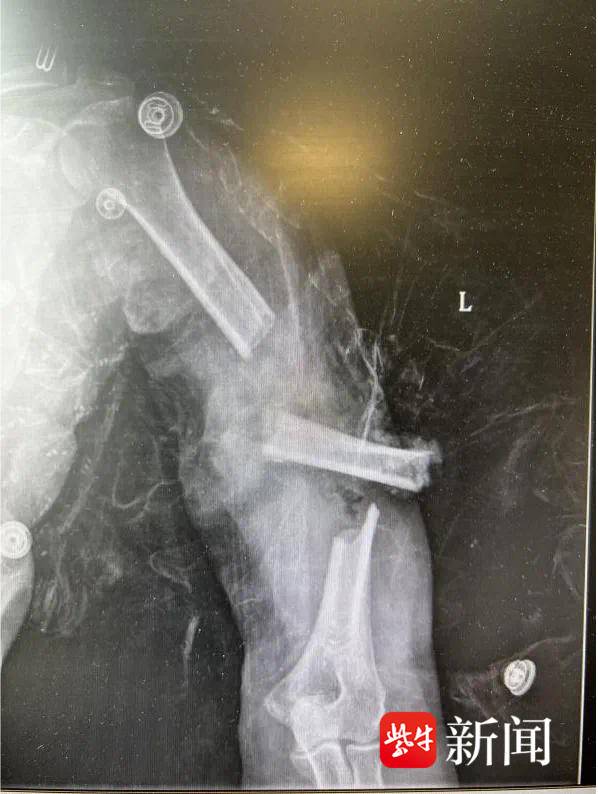

方阿姨是一名聋哑患者,今年60岁,在江心沙农场务农。事发当天,由于意外,她的左臂被割草机高速旋转的切割片“咬断”,造成了触目惊心的多发伤:左肱骨多段开放性粉碎性骨折伴中段骨块游离、左尺桡骨中段粉碎性骨折、左侧肩胛骨骨折、左膝后交叉韧带止点撕脱、右外踝骨折,还伴有左桡神经与肌皮神经严重损伤。

由于伤口污染严重且骨折情况复杂,医生先进行了彻底清创,并用外固定支架暂时固定骨折部位,同时探查修复受损的神经,放置引流管控制感染。